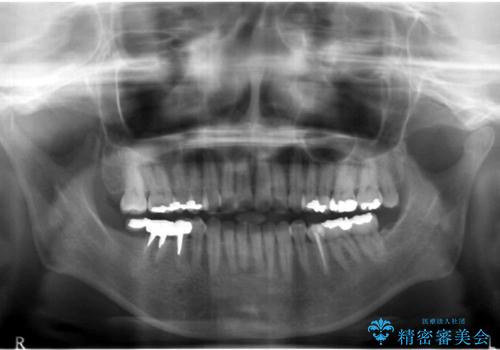

- 奥歯の痛みを主訴に来院された患者様です。

精査したところ、右下の奥歯(右下6)は割れており保存不可能な状態でした。

患者様のご希望により、右下大臼歯2本(右下76)のインプラント治療、右下小臼歯(右下5)の根管治療及び補綴治療を行いました。

割れていた歯の周囲組織の炎症が強く、骨の厚みが薄かったため、インプラント埋入時に骨増生(GBR)を行いました。